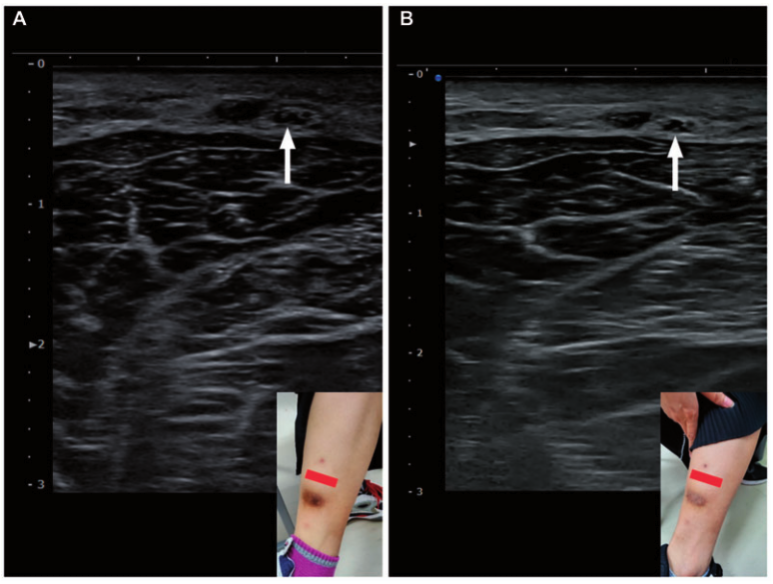

4. 초음파로 직접 확인하는 '진실의 순간'

이전에는

"증상을 보니 신경통 같네요"라고

추측만 했다면,

이제는 고해상도 초음파를 통해

눈으로 직접 확인할 수 있습니다.

doi: 10.1093/pm/pnac061

대만 환자는 흉터 밑에 눌린 신경이

단면적이 0.07cm²로 부어있었는데,

치료 후 0.04cm²로 정상화되었고요.

doi: 10.3928/01477447-20151020-15

미국 선수의 경우도

초음파상 신경 주변이 부어있고(부종)

흉터 조직에 엉겨 붙은 모습이

명확히 관찰되었습니다.

이렇게 초음파를 통해 신경이 붓고

주변 조직에 유착된 것을

실시간으로 확인하면

"아, 내 발이 아픈 게 꾀병이 아니라

진짜 신경이 눌려서 그렇구나"라고

환자분들이 비로소 안심하게 됩니다.